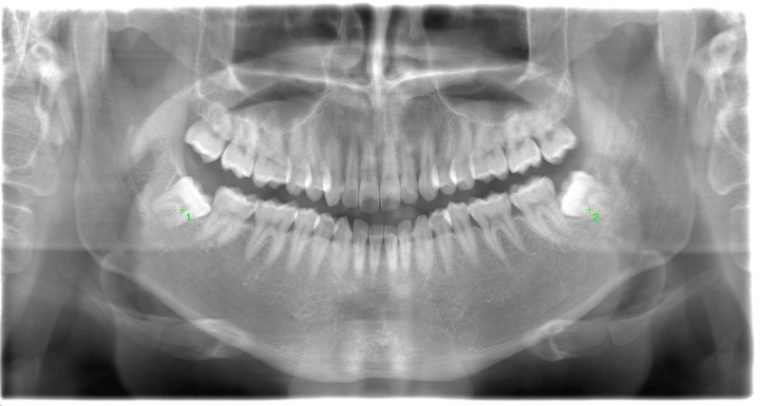

CASE 1

基本情報

| 年齢・性別 | 30代・女性 |

| 主訴 | 左右に分けて親知らずを抜きたい、できれば痛くなく抜きたい |

| 親知らずのはえ方 | 完全に出ていてまっすぐはえている |

| 抜歯期間 | 15分 |

| 抜歯費用 | 約2,000円(保険内) |

| 抜歯内容 |

何度か虫歯になり痛みはないが早めに抜きたい。 完全に頭が出ているため歯ぐきを切ったり骨を削らずに抜歯しました。 根の形も単純なため抜歯自体は5分もかからず上下ともに終わりました。 術後痛みや腫れも出ていません。 抜歯後は感染をしやすいため必ず抗生物質を飲み切ってください。 |